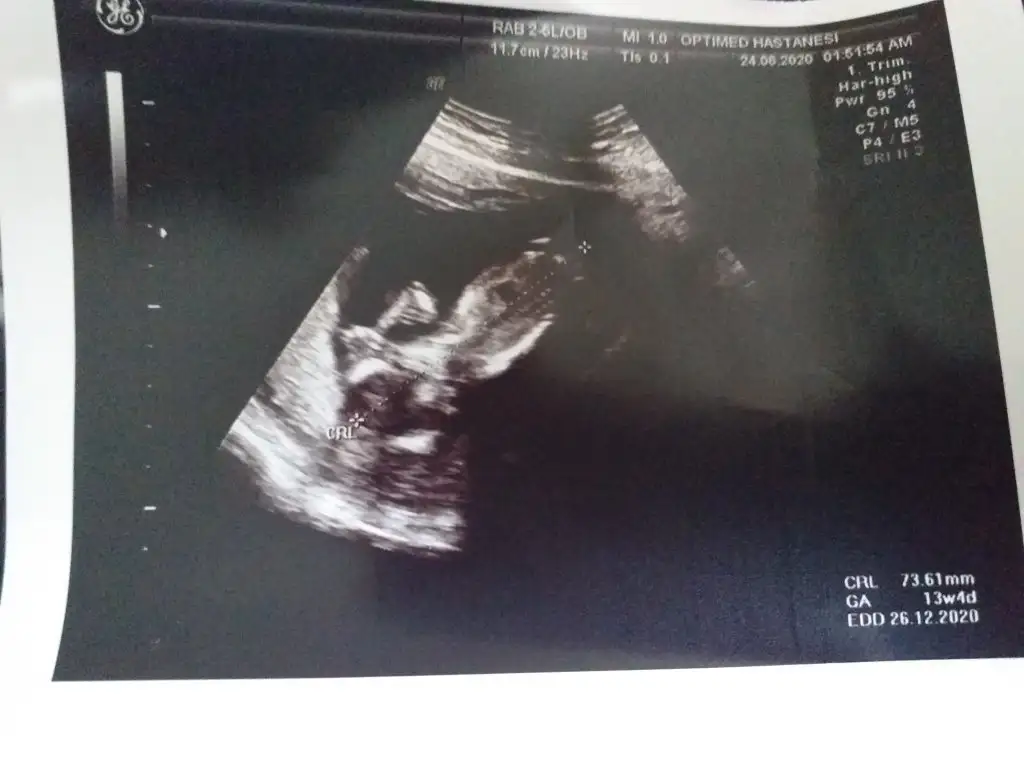

Erkek sankiElimde 13. hafta görüntüleri var 10. Haftada da gitmiştim. 11-12 maalesef yok

Yorumunuz için teşekkür ederim. 25 gün sonra randevum doktorum o zaman bakacağını söyledi. Belli olunca buraya yazarım. Vaktinizi ayırdınız tekrardan sağolunNet değil ama erkek sanki emin değilim bu usgde

Rabbim gönlünüzdekini saglıkla kucagınıza nasip etsin inşallahYorumunuz için teşekkür ederim. 25 gün sonra randevum doktorum o zaman bakacağını söyledi. Belli olunca buraya yazarım. Vaktinizi ayırdınız tekrardan sağolun